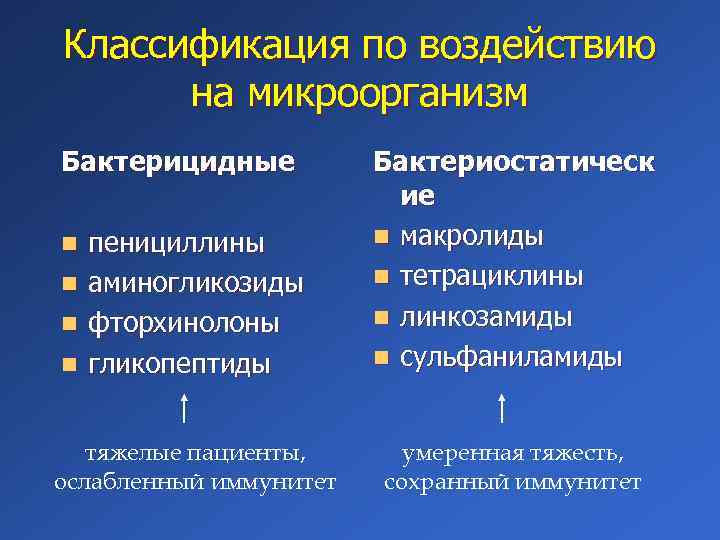

Механизмы действия антимикотиков: схемы и изображения